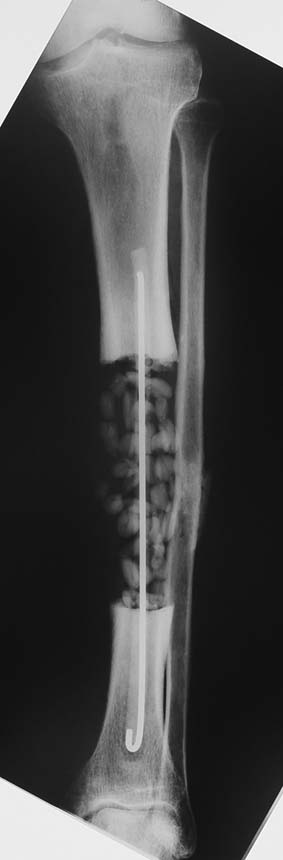

Uygun radikal debridman tüm nekrotik kemik ve yumuşak dokuların çıkartılmasını gerektirir, ve sıklıkla uzuvda instabiliteye neden olur. Kalan kemik ve yumuşak doku defektinin bir şekilde fiksasyonu ve rekonstrüksiyonu gereklidir. İlizarov’un ortaya koyduğu distraksiyon osteogenezi yöntemi, kaynamanın elde edilmesi, deformitenin düzeltilmesi, bacak boy eşitsizliğinin giderilmesi ve segmental defektlerin rekonstrükte edilmesi için başarıyla kullanılmaktadır.

Eksternal fiksatör ile geçen süre (eksternal fiksasyon indeksi), gereken distraksiyon miktarına bağlıdır ve bu süre boyunca bazı komplikasyonlarla karşılaşılabilir. Distraksiyon dönemi sona erdikten sonra, distraksiyon süresinin iki katını aşan konsolidasyon döneminde hastalar eksternal fiksatörü zorlukla tolere edebilirler. Yeterli konsolidasyon sağlanmadan eksternal fiksatör çıkartılırsa ise kırıklar, deformite ve kısalık oluşabilir. Hastanın fiksatör ile birlikte geçirdiği sürenin azaltılması ve böylece hasta konforunun ve aktivite düzeyinin arttırılması için intramedüller çivi üzerinden uzatma yöntemi uygulanmaktadır. Bu yöntemde distraksiyon dönemi sona erdiğinde kemiğin içindeki çivi statik olarak kilitlenmekte ve eksternal fiksatör çıkartılmaktadır. Stabilizasyon intramedüller çivi tarafından sağlandıktan sonra konsolidasyon dönemi gerçekleşmektedir. Bu şekilde hem eksternal fiksatörün uzun süre kalmasından hem de erken çıkartılmasından kaynaklanan komplikasyonların önüne geçilmektedir.